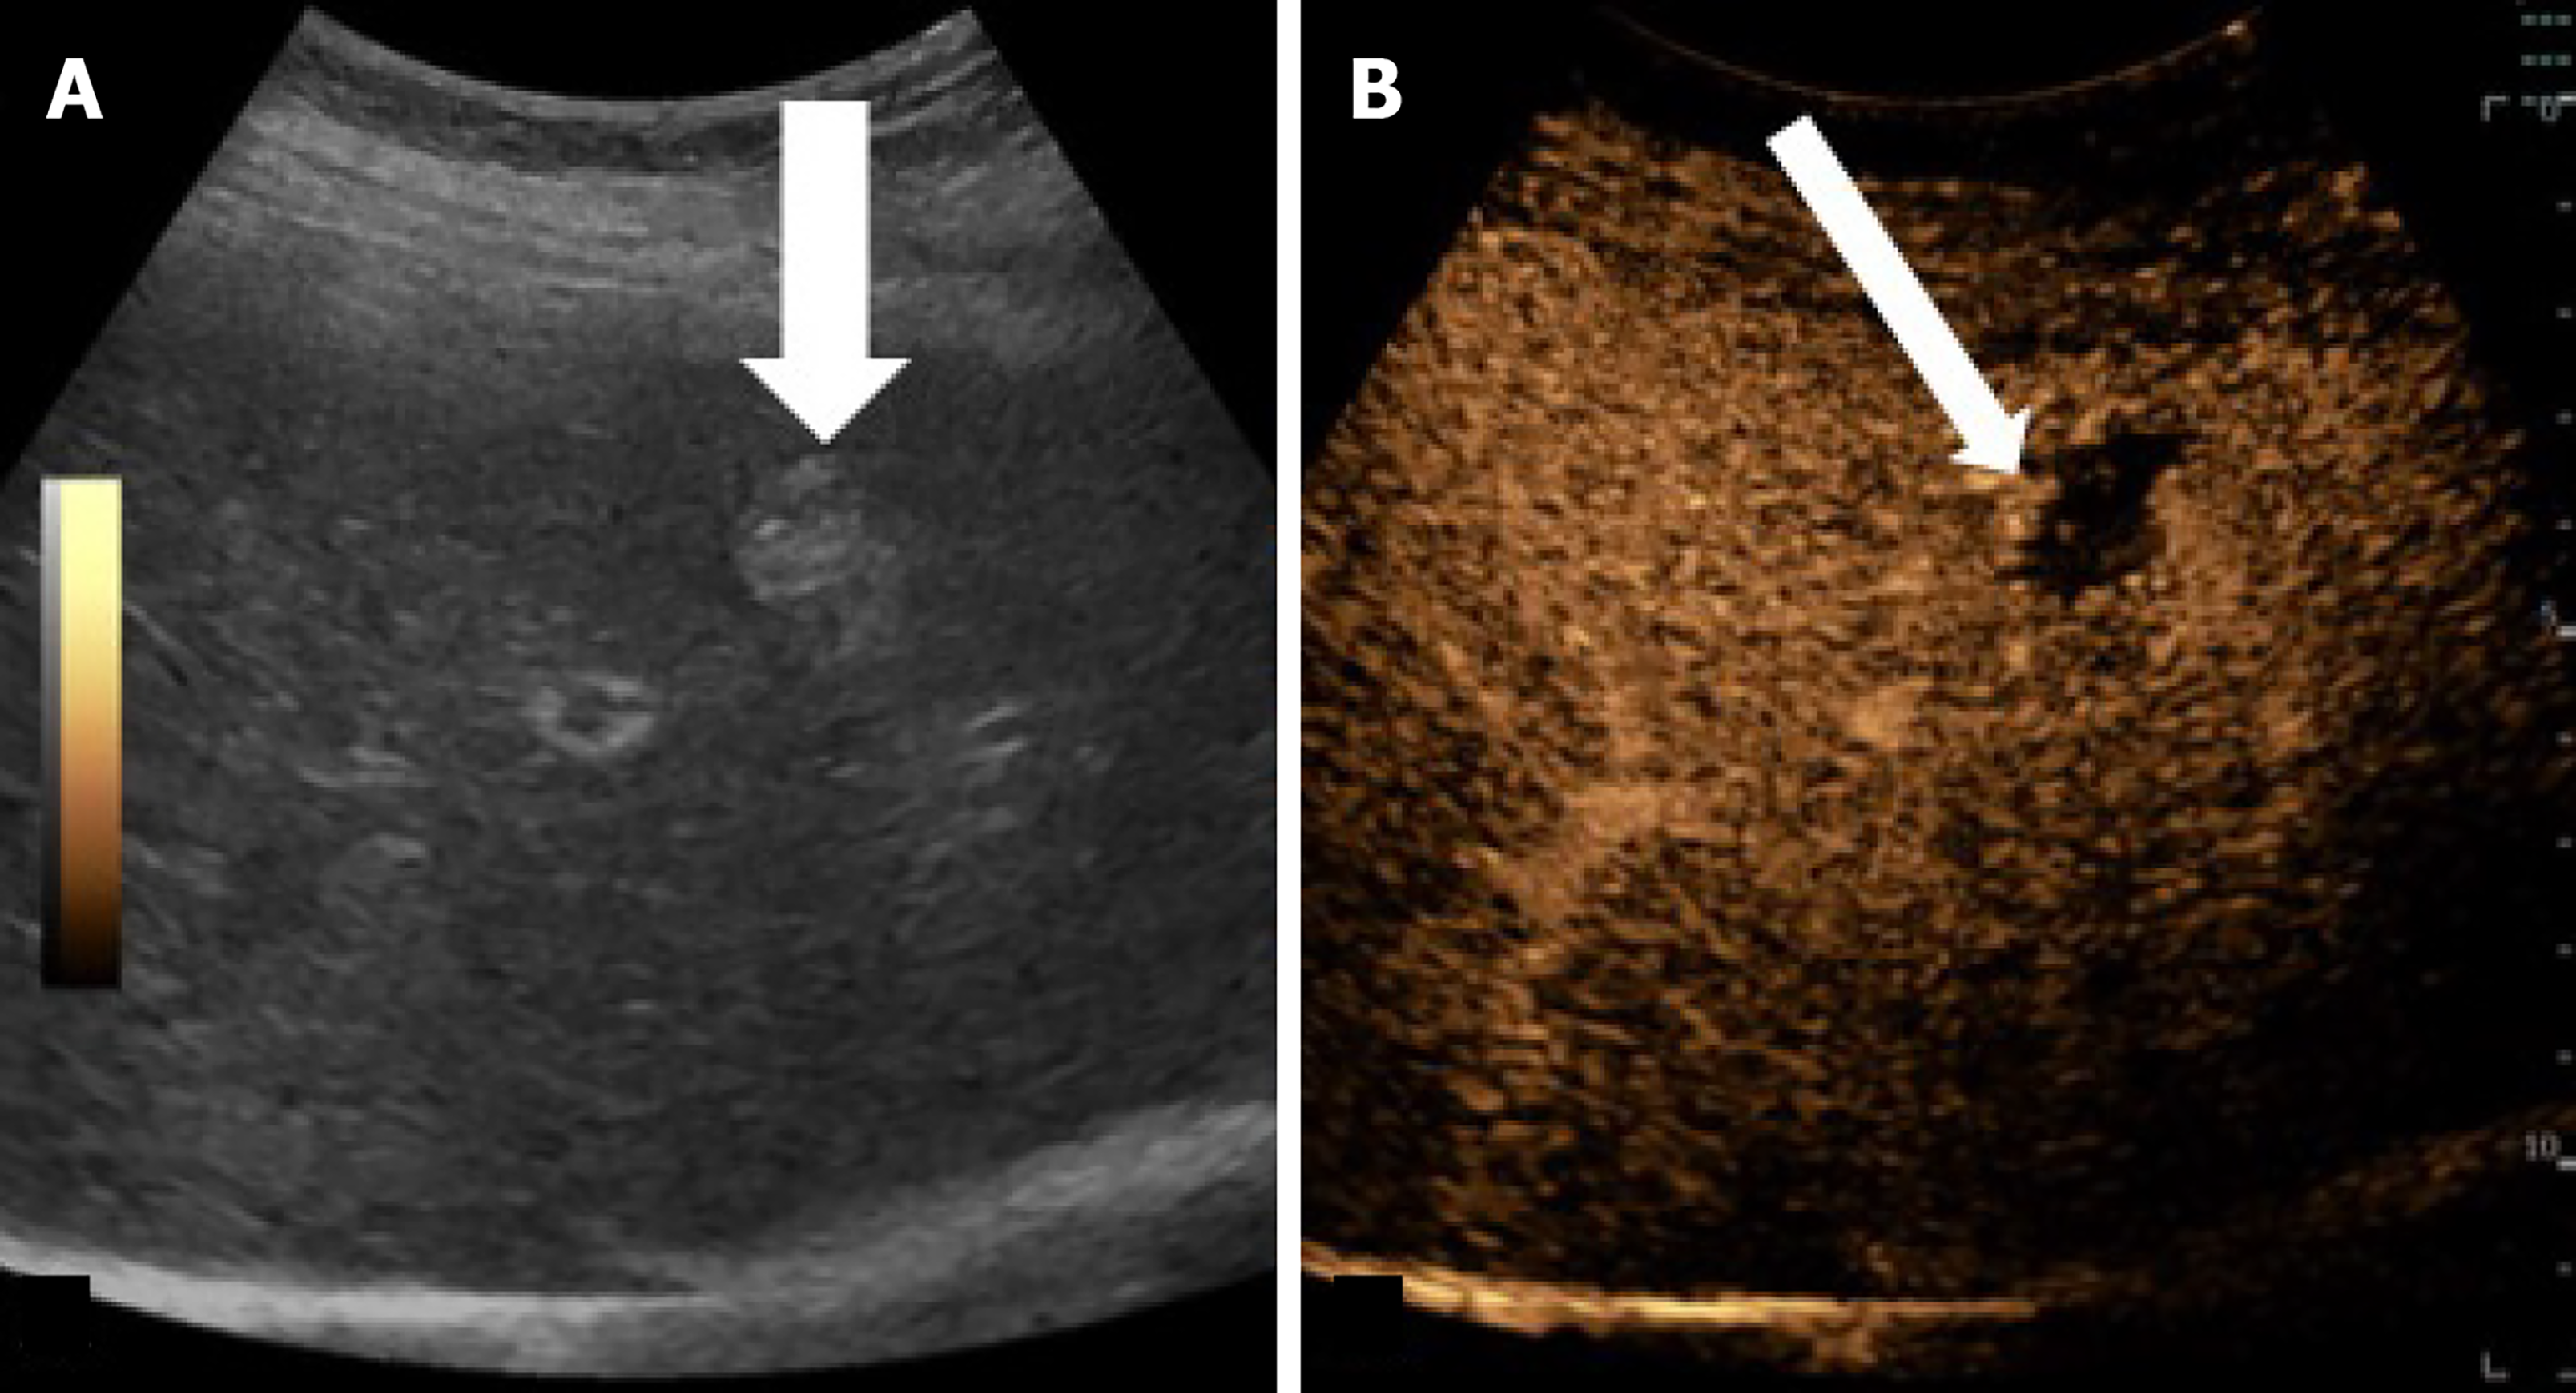

Figure 4 Recurrent hepatocellular carcinoma after radiofrequency ablation in an 82-year-old woman with hepatitis C virus-related cirrhosis.

A: On gray-scale ultrasound image obtained one year after radiofrequency ablation the treated area is hyperechoic nodule (arrow); B: Corresponding contrast enhanced ultrasound image achieved 18 s after injection shows a nodular are of hepatic arterial phase hyperenhancement (arrow).